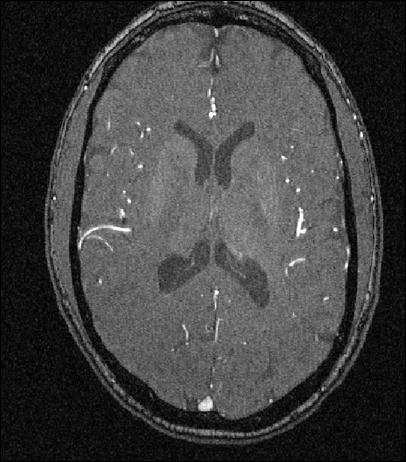

The data analyzed here are from a study of Magnetic Resonance Angiography brain images of a set of 737373 human subjects of both sexes, ranging in age from 181818 to 727272, which can be found at Handle (2008). One slice of one such image is shown in Figure 1. This mode of imaging indicates strong blood flow as white. These white regions are tracked in 333 dimensions, then combined, to give trees of brain arteries.

Refer to caption

Figure 1: Single Slice from a Magnetic Resonance Angiography image for one patient.  Bright regions indicate blood flow.